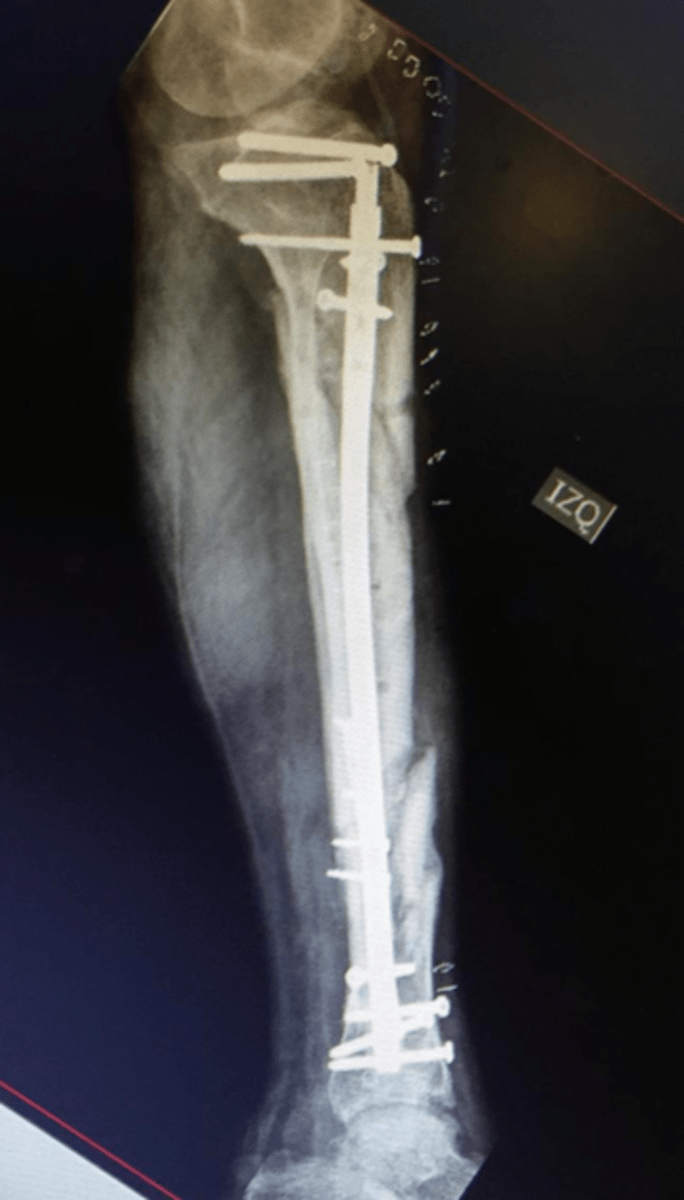

We will operate as first assist with the chief of trauma as well as other orthopaedic faculty and see patients in clinic. In addition to acute trauma, residents will also operate on complex trauma and subspecialty cases including chronic nonunions and malunions, limb deformity and salvage.

During our two weeks in Santiago, Chile we interacted with residents, fellows and attendings at various stages of training and practice. We reviewed complex Orthopaedic trauma cases and strategies in fixation and operated in a variety of settings. Although we were able to share our "American" perspective I think it was myself and my co-resident that I traveled with that were impacted the most. We were able to experience the extremes of chilean healthcare-from patients referred from the public hospitals with chronic nonunions who had been waiting and saving for surgery for years as well as the other end of the spectrum in the private hospital with resources beyond what we have in the US.